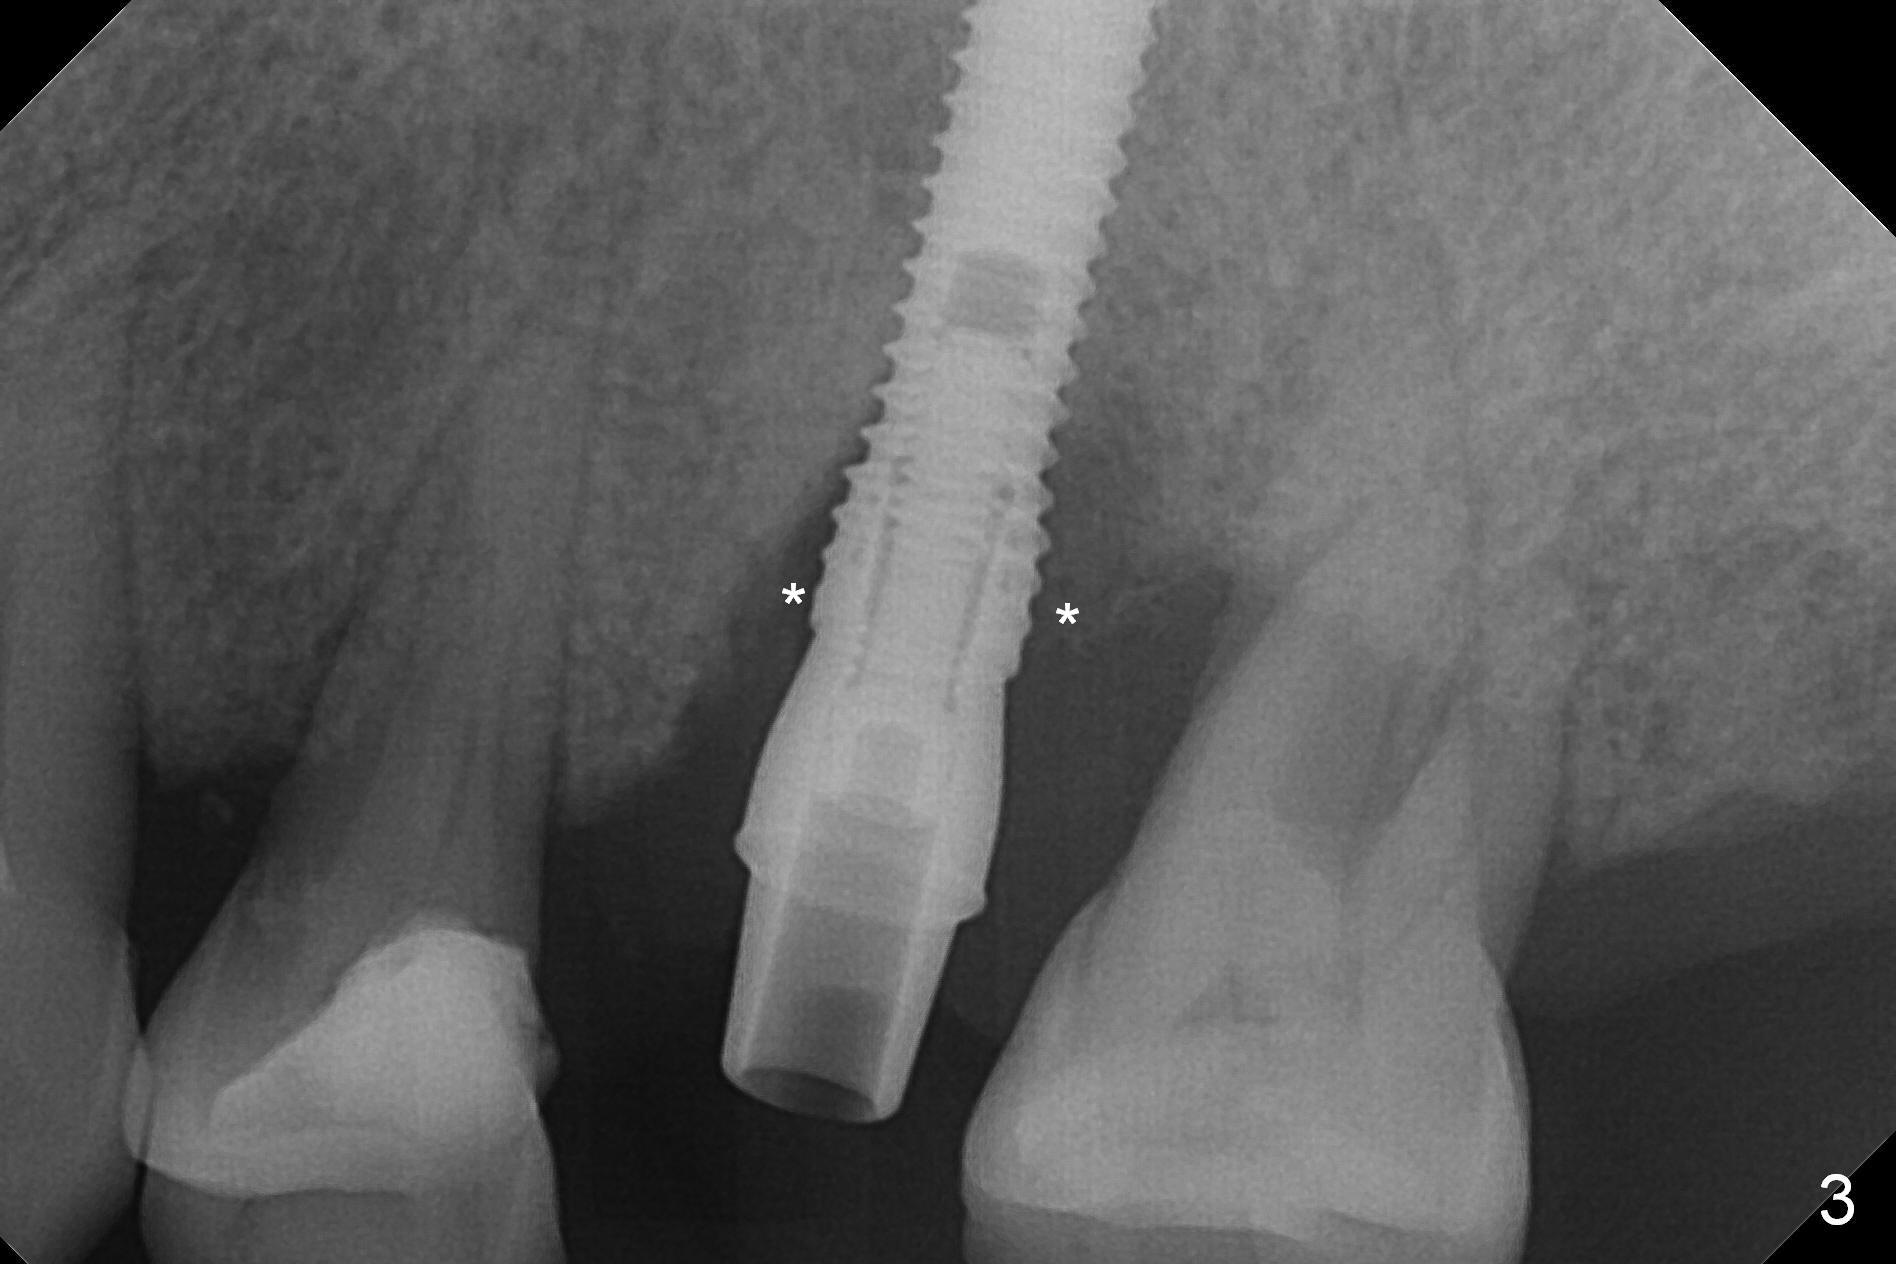

Initial osteotomy depth is 18 mm (Fig.1 green line) with 9 mm in the native bone (red line).  The bone density feels to be low.  There is at least 2 more mm bone apically (pink line).  The depth is increased by 2 mm so that when a 3.8x15 mm implant is placed, there is 10-11 mm implant/bone contact (Fig.2 red line).  There is large bony defect (Fig.3 *), which is bone grafted (Fig.4 *).  Finally a longer abutment is placed (4.5x5.5(5) in Fig.4 vs. 4.5x4(5) in Fig.2,3).  The 5 mm cuff does not look too long buccally (Fig.5) or palatally (Fig.6).   To prevent postop buccal gingival overgrowth (2), the buccal margin of an immediate provisional is subgingival (Fig.7-9 *).  Bone density between #13 and 14 appears to increase 3 months postop (Fig.10).  The implant seems to be equi-crestal (Fig.11 ^).  There seems to be more bone growth (i.e., decreasing gap) 6 months postop (Fig.12).  Impression is taken.  A crown is delivered nearly 7 months postop (08/07/2017).   While there is minimal bone loss at #13 and 15 three years and 4 months post cementation, the tooth #14 and 18 are mobile (Fig.13,14).